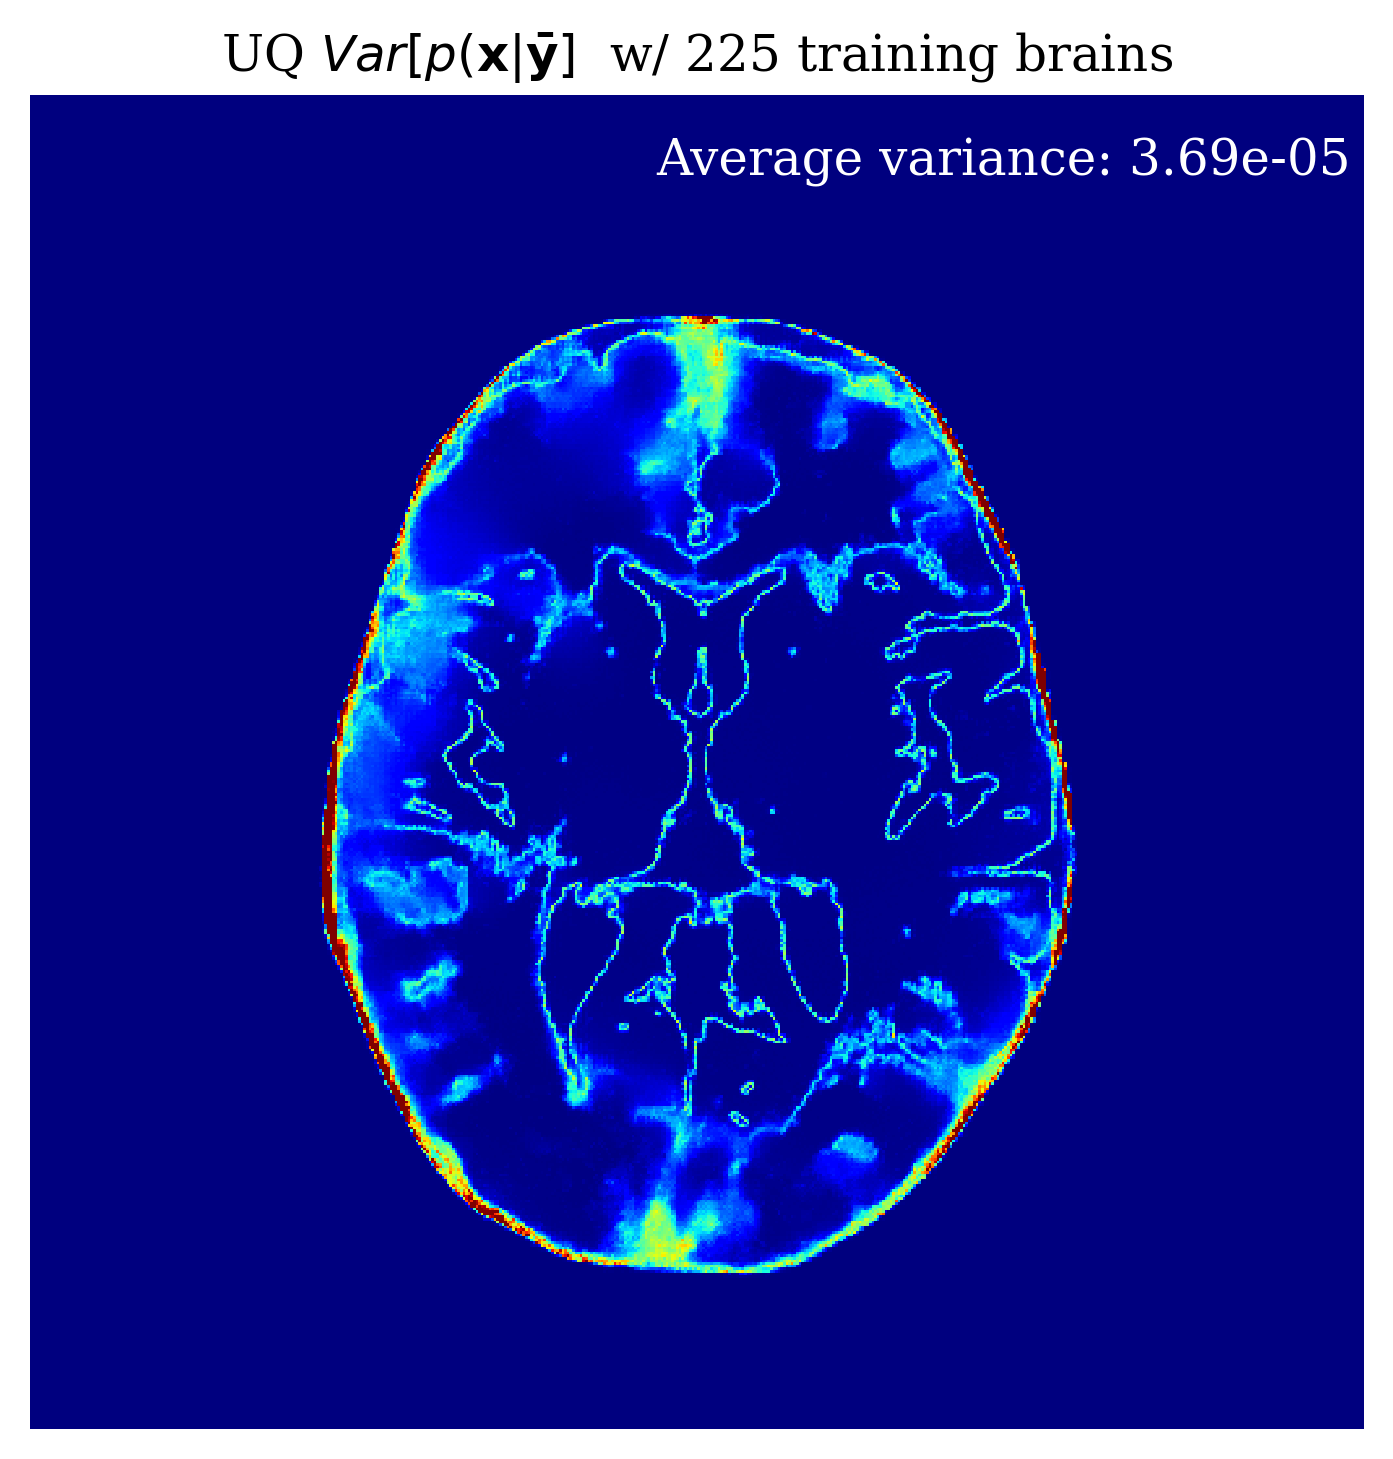

Since our method is Bayesian, its UQ results depend on how well it has learned the prior from training examples. In the case of conditional normalizing flows the prior is not explicitly accessible from the network since the network directly learns to sample the conditional distribution. Nonetheless, we would like to gain intuition on the effect of more training samples on the methods performance. In \figurereffig:trainingsize, we demonstrate the effect of increasing the training dataset size, on the posterior mean quality and on the UQ map that is produced. We observe from \figurereffig:trainingsize that as training samples increase, the posterior mean gets closer to the ground truth and that the UQ map becomes more contracted. These observations are similar to what happens when we increase the amount of observed data as explained in \sectionrefsec:uncertainty.

\subfigure

\subfigureUQ

\subfigureError

|